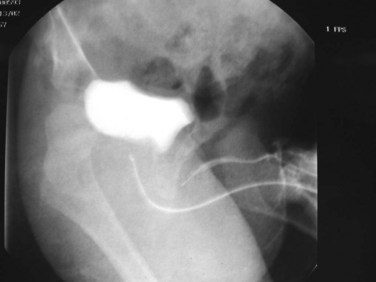

Young described type III valves as a membrane lying transversely across the urethra with a small perforation near its center (Fig. 126–3). The membrane is distal to the verumontanum and sometimes is elongated like a wind sock reaching the bulbous urethra (Field and Stephens, 1974). Type III valves make up only 5% of the total. Young described them as follows:

Figure 126–3 A, Voiding cystourethrogram demonstrates a typical type III posterior urethral valve with a transverse septum crossing the urethra at a right angle distal to the verumontanum. B, A cystoscopic image from the distal urethra shows the thin membrane and a small off-center opening.